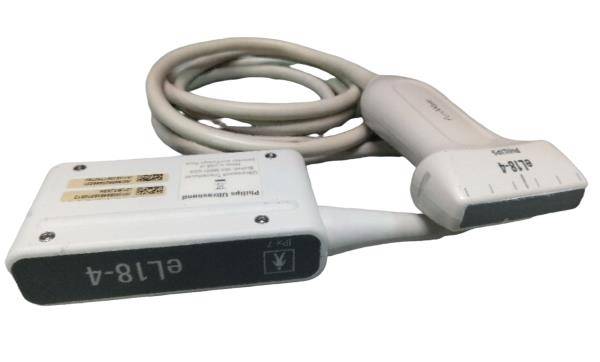

Description

Condition:Manufacturer refurbished : An item that has been professionally restored to working order by a manufacturer or manufacturer-approved vendor. This means the product has been inspected, cleaned, and repaired to meet manufacturer specifications and is in excellent condition. This item may or may not be in the original packaging. See the sellerâs listing for full details. See all condition definitions- opens in a new window or tab

Seller Notes:âGreat Condition!! - Manufacturer (GE) Refurbished!!â

Brand: LOGIQ E